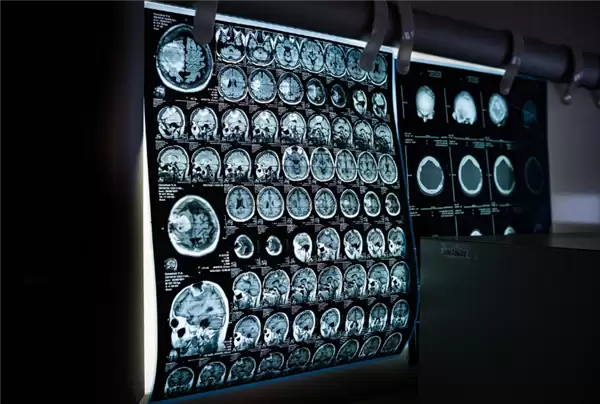

异地就医不带片!医学影像全国“漫游”正式开启

11月21日,一则医疗领域的消息引发关注。据媒体报道,北京大学第三医院的医生通过全国统一的医保影像云系统,在线调阅了来自福建三明地区一位患者的电子影像资料,结合现场快速检查,很快就完成了诊断并给出专业医嘱。

这标志着全国医保影像云跨省调阅服务正式落地启动。未来,异地就医的患者将普遍享受到这项便捷服务,不必再为携带影像资料奔波。

近年来,国家医保局持续推进医疗影像“上云”工程,要求各级医疗机构将影像数据集中上传至云端统一存储管理,实现跨机构信息共享。

同时,全国医保影像云“一张网”正在加速构建,支撑“患者可阅片、医生可查阅、医保可审核”的新型业务协同机制。这一系统为解决患者重复检查带来的时间、精力和费用问题奠定了坚实基础。

截至11月20日,全国已有北京、河北、山西等24个省份及新疆生产建设兵团完成了医保影像云系统的省级部署,具备了省级平台影像索引数据上传与跨省调阅能力。最新数据显示,国家医保局汇聚的影像索引数据总量已达1.7亿条。

随着系统覆盖范围不断扩大,影像互联互通服务将逐步延伸至更多省份及基层医疗机构。专家表示,这一系统最终将实现医学影像在全国范围内的高效流转与协同应用。